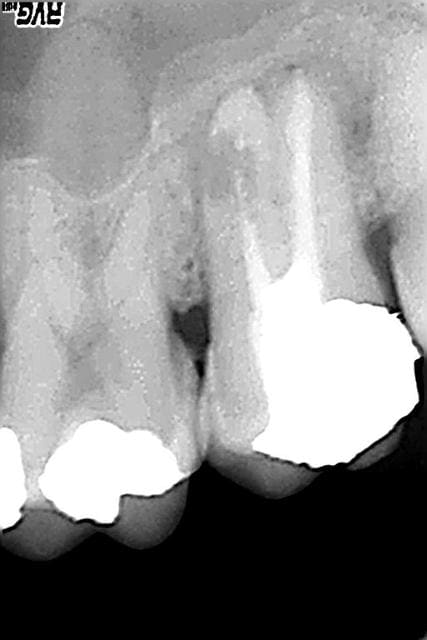

... des résorptions internes.